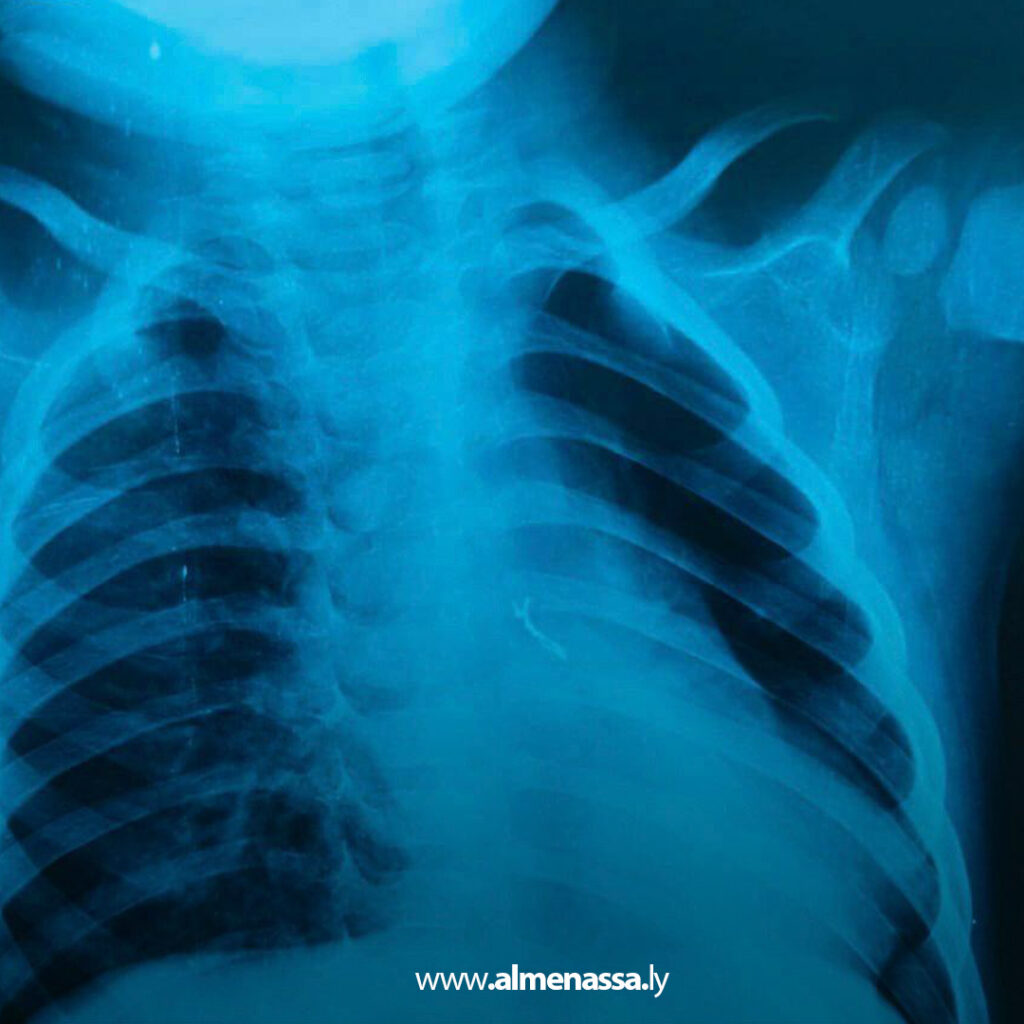

وأظهرت الفحوصات الأولية، إلى جانب التصوير الإشعاعي، وجود جسم غريب مجهول المصدر داخل القصيبات الهوائية اليسرى، وهو ما فسّر تكرار الالتهابات التنفسية وصعوبة التنفس التي كان يعاني منها الرضيع.

وعلى إثر ذلك، اعتبرت الحالة طبية طارئة تتطلب تدخلًا فوريًا لتفادي حدوث انسداد هوائي أو التهابات رئوية حادة قد تهدد حياته.

بناء على نتائج الفحوصات، تقرر إجراء منظار قصبات مستعجل، حيث جرى تجهيز غرفة العمليات وفق أعلى معايير السلامة، وتم التعامل مع الحالة بدقة متناهية نظرًا لصغر سن الطفل وحساسية الإجراء. وتمكن الفريق الطبي من استخراج الجسم الغريب بنجاح، دون تسجيل أي مضاعفات أثناء أو بعد العملية.